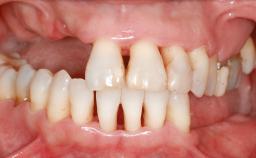

Ridge Preservation and Implant Placement for a Fixed Dental Prosthesis After a Car Accident

It is well known to clinicians that any removal of teeth will, over time, cause the dimensions of the alveolar ridge to be reduced by resorption of the bundle bone and by changes related to external modeling. This development is particularly evident in the crestal region with its thin buccal bone that consists of bundle bone almost entirely. The facial bone will rapidly resorb as blood supply from the periodontal ligament gets disrupted (Araújo and Lindhe 2005). There is no reason why traumatic tooth loss should not have the same consequences. It takes more than achieving implant osseointegration for a treatment outcome to be considered successful. No deficiency of bone or soft tissue is acceptable when an ideal esthetic outcome is the goal. Several articles (Sanz and coworkers 2011; Vignoletti and coworkers 2011) have reported on techniques of improving the alveolar ridge for implant treatment, notably focusing on protecting tissues from resorption.

Lip Line No exposure of papillae Exposure of papillae Full exposure of mucosa margin

Periodontal Phenotype Low-scalloped, thick Medium-scalloped, medium-thick High-scalloped, thin

Shape of Tooth Crowns Rectangular Triangular

Soft Tissue Anatomy Intact Defective

Bone Volume Horizontally and vertically sufficient Horizontally deficient Deficient vertically or deficient vertically AND horizontally